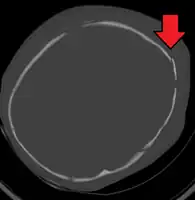

A skull fracture from abusive head trauma in an infant -

3D CT reconstruction showing a skull fracture in an infant -

3D CT reconstruction showing a skull fracture in an infant

Diagnosis can be difficult as symptoms may be nonspecific.[1] A CT scan of the head is typically recommended if a concern is present.[1] While retinal bleeding is common, it can also occur in other conditions.[1] It is unclear how useful subdural haematoma, retinal hemorrhages, and encephalopathy are alone at making the diagnosis.[23]